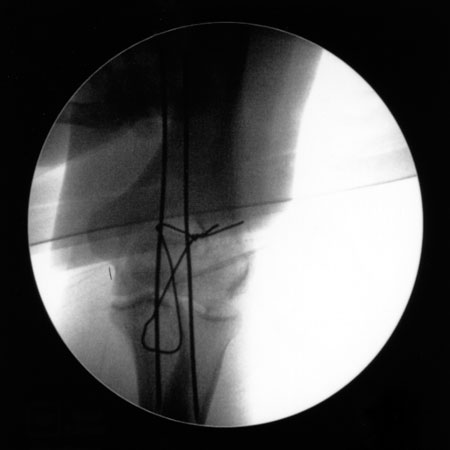

Above is the smashed elbow at the beginning of the operation. In hindsight, it would appear that only a complete idiot would run around the snowed-in, icy Dolomites for an entire week (including a six-hour tour at high altitude) with this before seeing a doctor.

These images show the repositioning of various bone fragments (after cleaning the joint from blood and debris), and the step-by-step insertion of wires that pull the fragments into their correct position in the coming months.